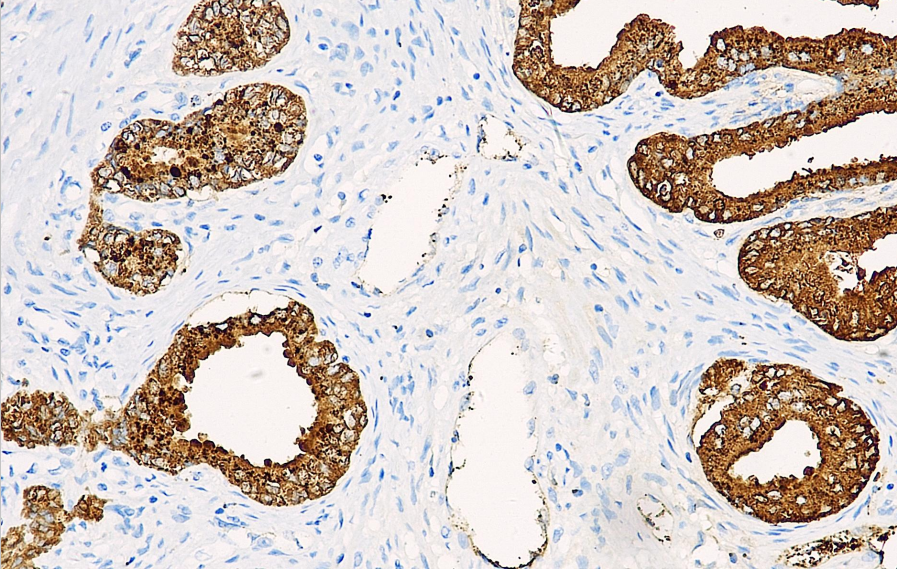

Positive control: prostate/prostate cancer

PSAP (Prostatic Specific Acid Phosphatase) is an isoenzyme of acid phosphatase secreted by prostate epithelial cells and is expressed in normal prostate tissue, hyperplastic prostate tissue, and prostate cancer. This antibody is primarily used for research on prostate cancer and metastatic prostate cancer, but it cannot be used for research on benign or malignant prostate diseases.

PSAP antibody reagents can specifically bind to PSAP molecular antigens. Immunohistochemistry kits containing PSAP antibody reagents are suitable for the auxiliary diagnosis of prostate cancer and metastatic prostate cancer.